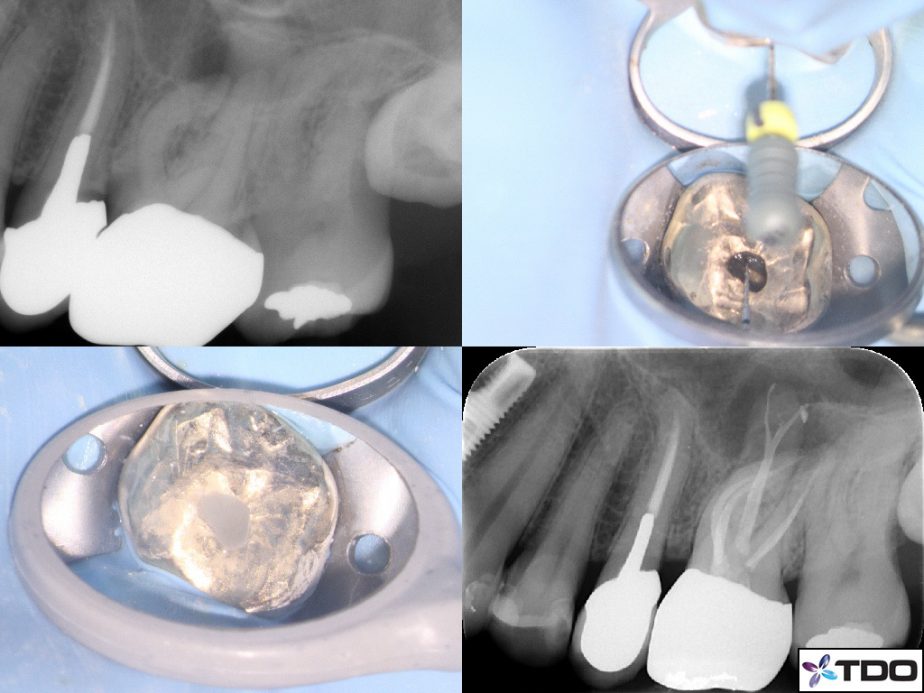

Patient C presented with an acutely painful tooth 26. The tooth had a full gold crown placed a couple years prior and had been asymptomatic up until the recent development of pain. Orthograde endodontic treatment was performed for the tooth over two visits with calcium hydroxide dressing.

At the first visit, the tooth was conservatively accessed and irrigated with NaOCl. There were four canals located and cleaned. The Mb1 and Mb2 canals were curved and required several passes with hand files no 8,10, 15 prior to create a glide path. Shaping of the canals was achieved with ProFile Vortex Blue instrumentation 15, 20, 25, 30.

One week after debridement was completed Patient C was asymptomatic, and the tooth was obturated with gutta percha and AH Plus sealer. A deep palatal split was obturated via the warm vertical obturation technique.

A composite resin restoration was placed to close the access. The patient is scheduled for endodontic review at 6 months.